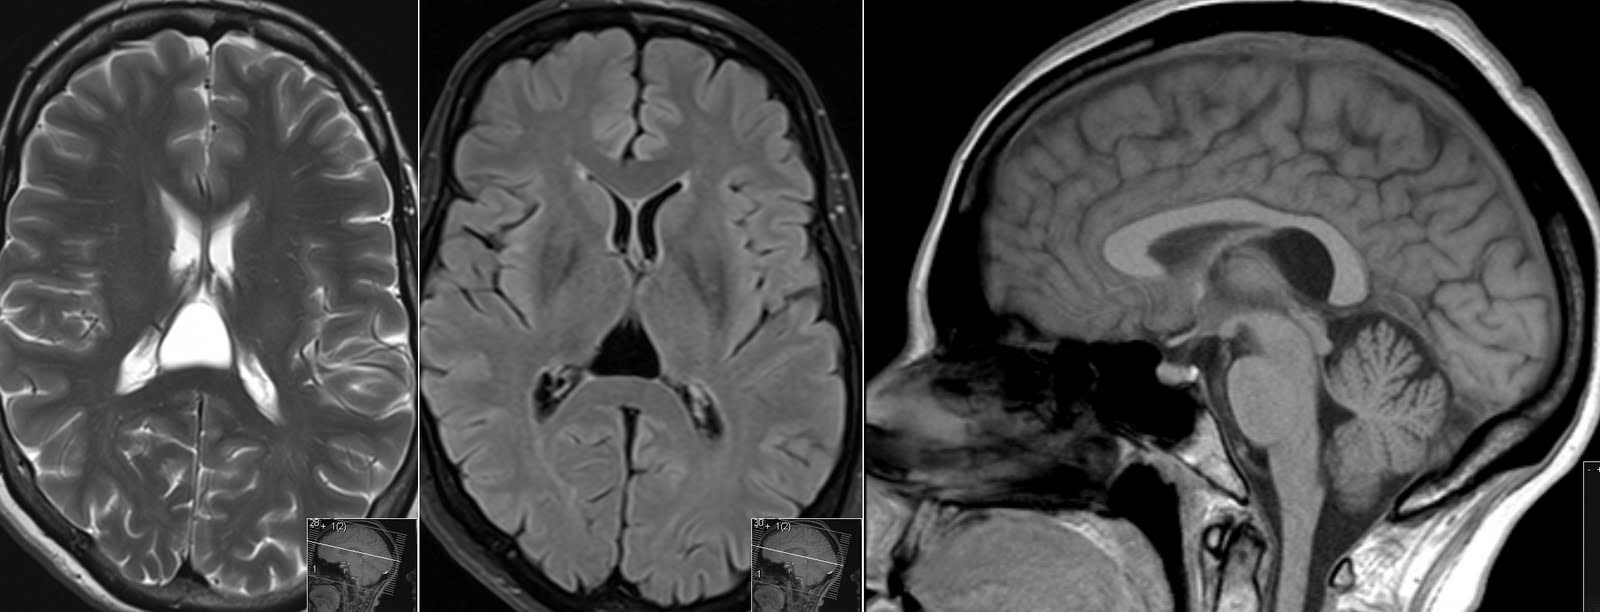

Прозрачная перегородка кт

Прозрачная перегородка кт 115 фотографий